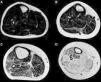

Variabilidad en el tamaño y posición del ROI: el reemplazo graso no suele darse como un aumento difuso de la señal del músculo afectado. Muy por el contrario, el cambio en resonancia suele verse tanto como áreas de músculo con señal relativamente normal que se alternan con tractos adiposos de alta señal, como áreas grises, más uniformes de límites variados, cambios que con frecuencia son progresivos (fig. 4). La elección de un ROI de pequeño tamaño, en forma aislada, puede determinar la elevación o normalización de la señal en un rango que puede llegar hasta el 80%, dependiendo la posición respecto de la presencia de áreas relativamente más preservadas o áreas de franca infiltración (fig. 5). La selección de múltiples mediciones en una misma área o de un área que se acerque a los límites del músculo permite dar cuenta, en una medida promedio, de la coexistencia de tractos fibrosos de diferente calibre y de fibras musculares preservadas. Al evaluar la diferencia entre realizar varias mediciones pequeñas y una medida que abarque el total del músculo, no existieron diferencias significativas entre el promedio aritmético de los valores de los 5 ROI pequeños y el valor de un ROI del área de sección para 107 músculos por paciente (p=0,0749).

Variabilidad intramuscular e intermuscular: en pacientes sanos se estimó una fracción grasa promedio, para todos los músculos, cercana al 5%. Los promedios de variabilidad en los músculos analizados por segmentos fueron bajos en este grupo, con cambios no superiores al 2%. Una leve mayor variación fue observada en músculos como el glúteo mayor o los extensores lumbares, con variación entre 2,3 y 10,4%. En pacientes portadores de miopatía congénita existe una mayor variabilidad en los promedios de registro de la fracción grasa para un mismo músculo (fig. 6). La variabilidad intramuscular en estos pacientes se estimó en 4,8%, con rango de 3,1-7,8%. La mayor variabilidad se observó en músculos extensores dorso-lumbar, flexores del hallux, sartorio, vasto lateral y vasto intermedio. No existe correlación entre la variabilidad intramuscular de la fracción grasa medida en músculos de pacientes sanos, respecto de pacientes portadores de miopatía congénita (fig. 7). La media aritmética, obtenida para cada segmento, no mostró diferencias claras en la evaluación de los músculos largos, en pacientes portadores de miopatía congénita (fig. 8).

Sin embargo, a pesar de la utilidad previamente demostrada en la literatura de la técnica de Dixon para cuantificar el reemplazo graso, las mediciones aisladas son insuficientes para su valoración objetiva. Los patrones de reemplazo intramuscular, descritos por Goutallier et al. en 199425,26, subrayan el hecho anatómico de la coexistencia de áreas más preservadas de músculo alternadas con estrías grasas más numerosas y de mayor tamaño, y coinciden con la mayor variabilidad de la fracción grasa en pacientes portadores de miopatías congénitas en nuestro estudio. La ausencia de relación entre la variabilidad de la fracción grasa, en pacientes sanos y enfermos, da cuenta del reemplazo heterogéneo de las fibras musculares por grasa, como una condición propia de la enfermedad.